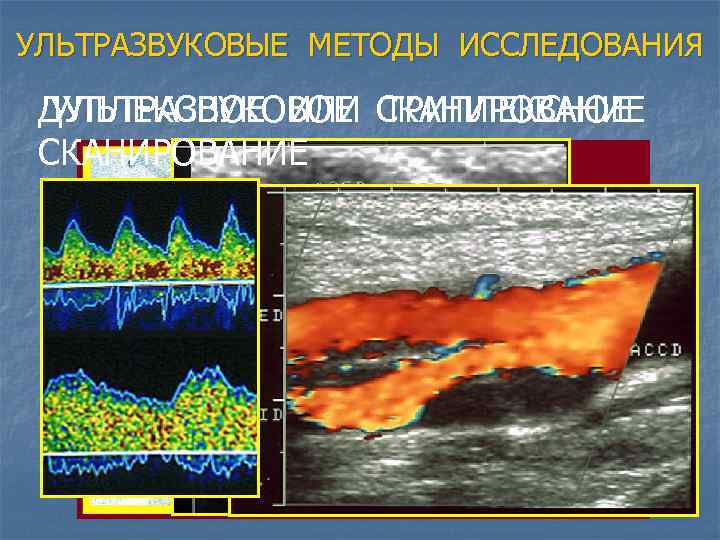

УЛЬТРАЗВУКОВЫЕ МЕТОДЫ ИССЛЕДОВАНИЯ ДУПЛЕКСНОЕ ИЛИ СКАНИРОВАНИЕ УЛЬТРАЗВУКОВОЕ ТРИПЛЕКСНОЕ СКАНИРОВАНИЕ